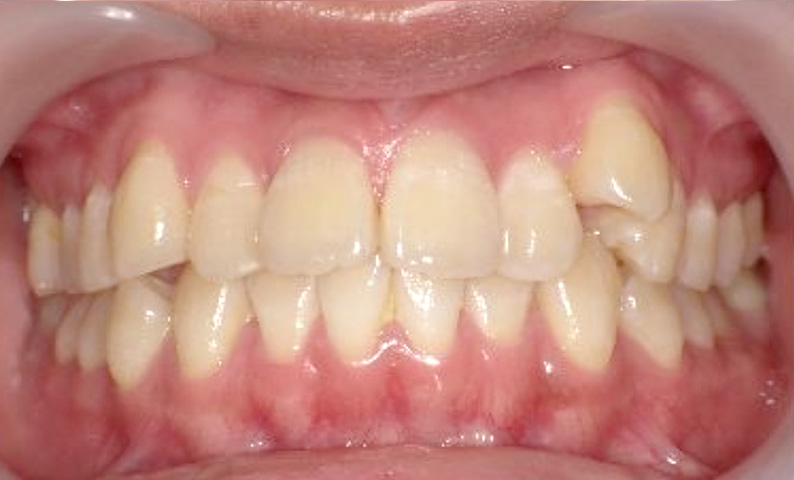

症例_005 上下顎の部分矯正

治療期間:11ヶ月金額:54万円+税女性前歯のガタガタ捻転歯

| Before | After |

|---|---|

|